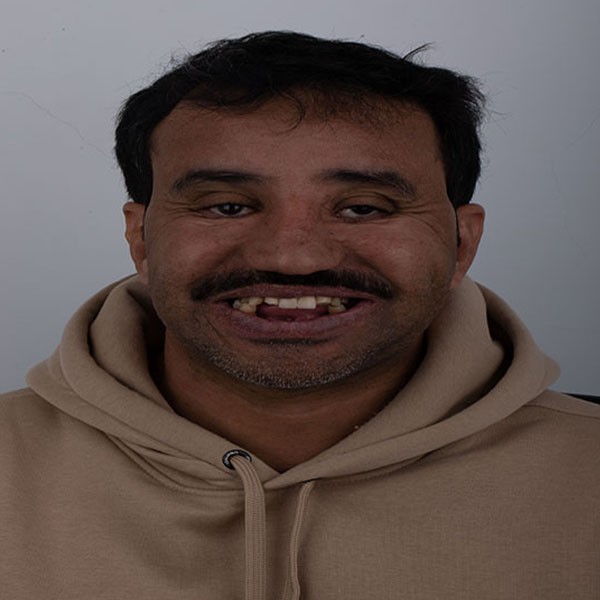

Founded in 2012, our clinic has over a decade of trusted experience in delivering world-class dental care. We specialize in full mouth rehabilitation and implantology, while also offering comprehensive services across all dental specialties including fixed and removable prosthodontics, restorative, endodontics, periodontics, maxillofacial surgery, orthodontics, and pediatric dentistry. Our strength lies in our dedicated team of highly skilled dentists, each bringing diverse expertise, working together with a shared passion for teamwork to ensure every patient receives a personalized care. Equipped with a state-of-the-art CAD/CAM lab, in-house CBCT, and panoramic X-ray technology, we provide a seamless workflow and the convenience of same-day crown deliveries. Our commitment is to combine expertise, precision, and the latest innovations in modern dentistry to create healthy, confident smiles in a professional and welcoming environment.